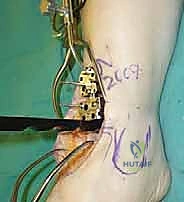

4. وضع أدلة القطع (Jig Placement and Alignment)

تعتمد دقة الجراحة على المحاذاة الصحيحة. يتم استخدام أجهزة توجيه متطورة (Jigs) تثبت على عظمة الساق باستخدام دبابيس معدنية. يتم التحقق من صحة الزوايا والمحاور باستخدام جهاز الأشعة السينية المباشر داخل غرفة العمليات (C-arm Fluoroscopy). يضمن الدكتور هطيف أن يكون القطع موازياً للأرض تماماً عند وقوف المريض.

5. القطع العظمي الظنبوبي (Tibial Bone Cut)

باستخدام منشار جراحي دقيق التذبذب، يتم إزالة شريحة رقيقة جداً (بضعة مليمترات) من السطح السفلي التالف لعظمة الظنبوب. يتم القطع بحذر شديد لتجنب إصابة الأوتار الخلفية أو الأوعية الدموية.